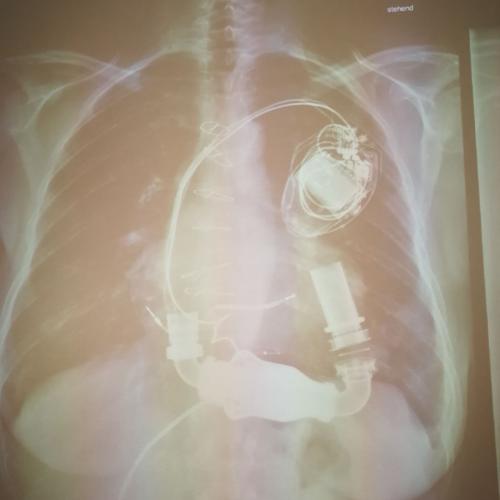

Der spannendste Teil seines Besuchs war die Vorstellung von „Kunstherzen“. Dr. Höfer hatte verschiedene Modelle von pulsierenden Unterstützungssystemen dabei, die Patienten mit schwerer Herzschwäche unterstützen oder sogar das Herz vollständig ersetzen können. Er erklärte, dass solche Kunstherzen oft als Übergangslösung bis zu einer Herztransplantation genutzt werden. Zudem gab er uns eine Demonstration eines solchen Kunstherzens mit der Hilfe von Wasser, welches Blut darstellen sollte. Ein besonderes Highlight war ein echtes Operationsvideo, das zeigte, wie ein Kunstherz chirurgisch eingesetzt wird. Es war beeindruckend zu sehen, wie präzise Chirurgen arbeiten müssen, um ein Leben zu retten.